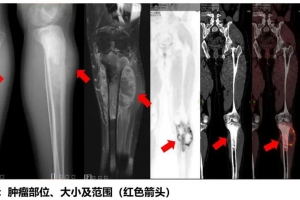

A Case Report - Osteosarcoma Invades The Knee Joint, Liquid Nitrogen For Cryotherapy Treatment Saves..